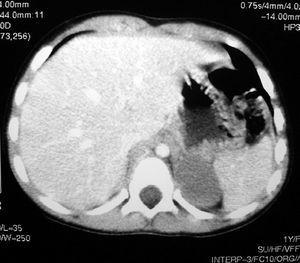

Ante la sospecha de neoplasia adrenocortical productora de andrógenos se solicitan hormona adrenocorticotropa (ACTH) 20 pg/ml (valor normal [VN]: 10-55 pg/ml), cortisol basal plasmático 8,9 µg/dl (VN: 7-26 µg/dl), testosterona 2,5 ng/ml (VN = < 1 ng/ml), deshidroepiandrostendiona sulfato (SDHEA) 615 µg/dl (VN: 82-300 µg/dl). Con objeto de descartar el neuroblastoma así como la existencia de metástasis, se realizan catecolaminas en sangre y orina (normales) y una tomografía computarizada (TC) que confirma los hallazgos ecográficos sin encontrarse invasión aparente de áreas vecinas ni metástasis en hígado o pulmón (fig. 2).

Figura 2.TC toraco-abdominal.